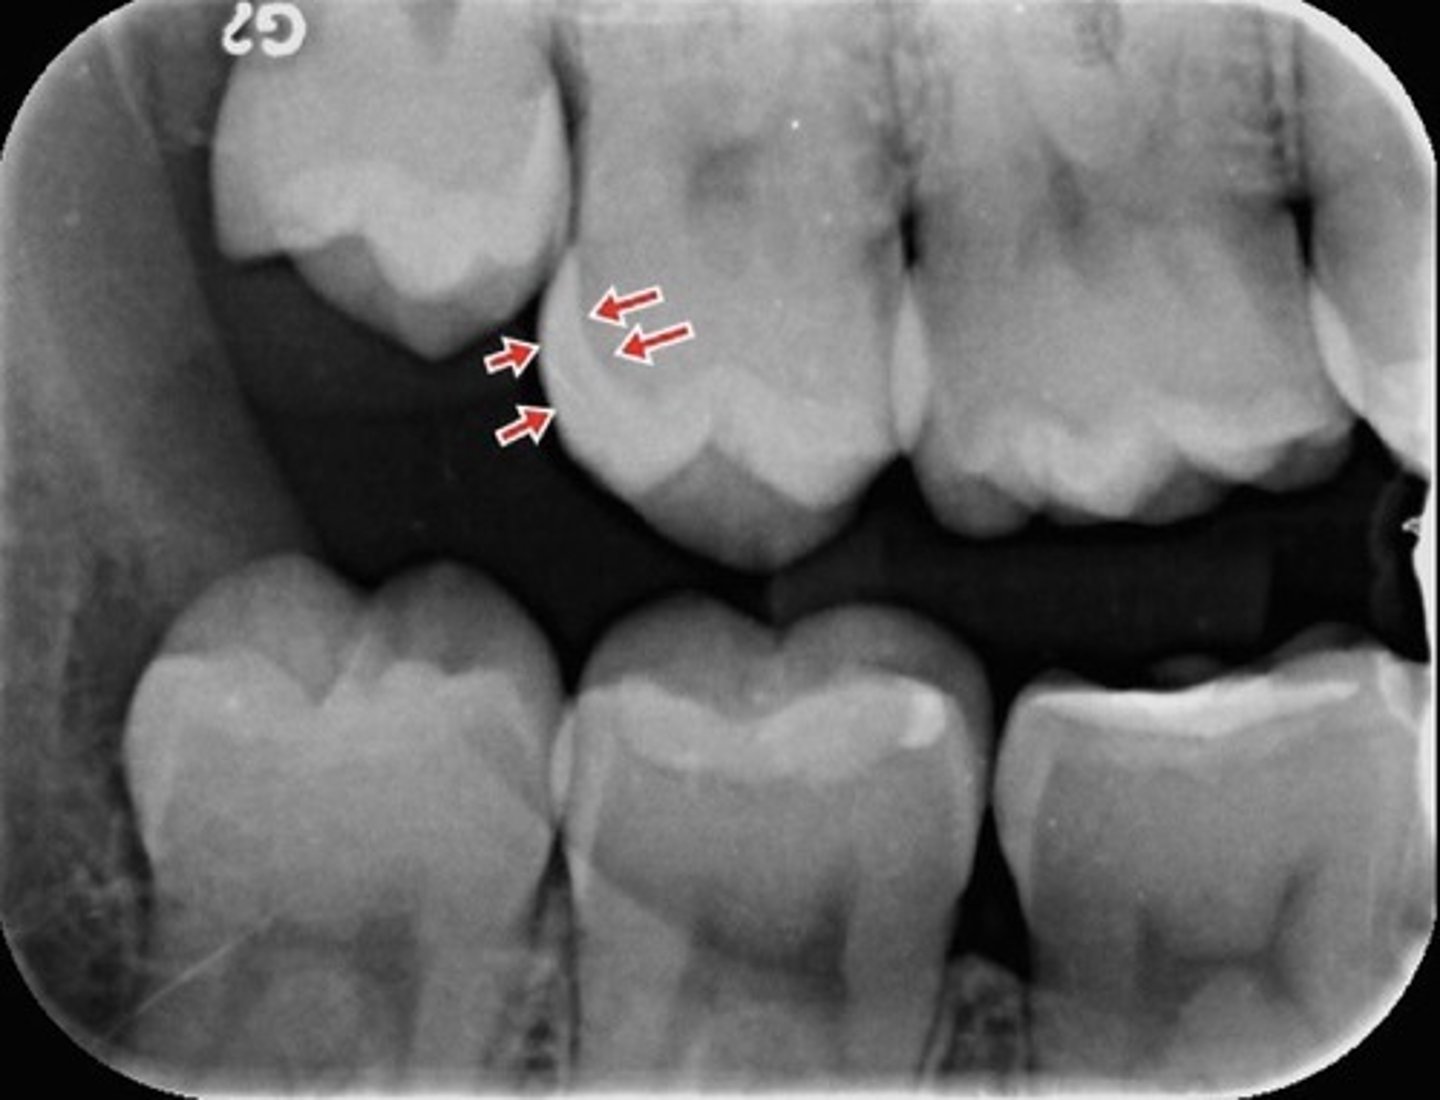

Enamel

What is the arrow pointing to?

What are the red arrows pointing to?

Alveolar crest

Alveolar bone